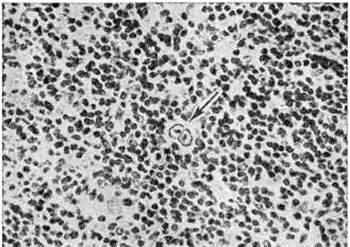

Рис. 2.

Микропрепарат лимфатического узла при лимфогистиоцитарном типе лимфогранулематоза: видна пролиферация лимфоцитов, стрелкой указана клетка Березовского — Штернберга.

Лимфогистиоцитарный тип Лимфогранулематоз характеризуется преобладанием лимфоидной пролиферации, сочетающейся с различной степенью пролиферации гистиоцитов. Пролиферация клеток может носить очаговый или диффузный характер, эозинофилы и плазматические клетки располагаются неравномерно, гигантские клетки Березовского—Штернберга встречаются редко; обычно отсутствуют очаги некроза (рисунок 2).